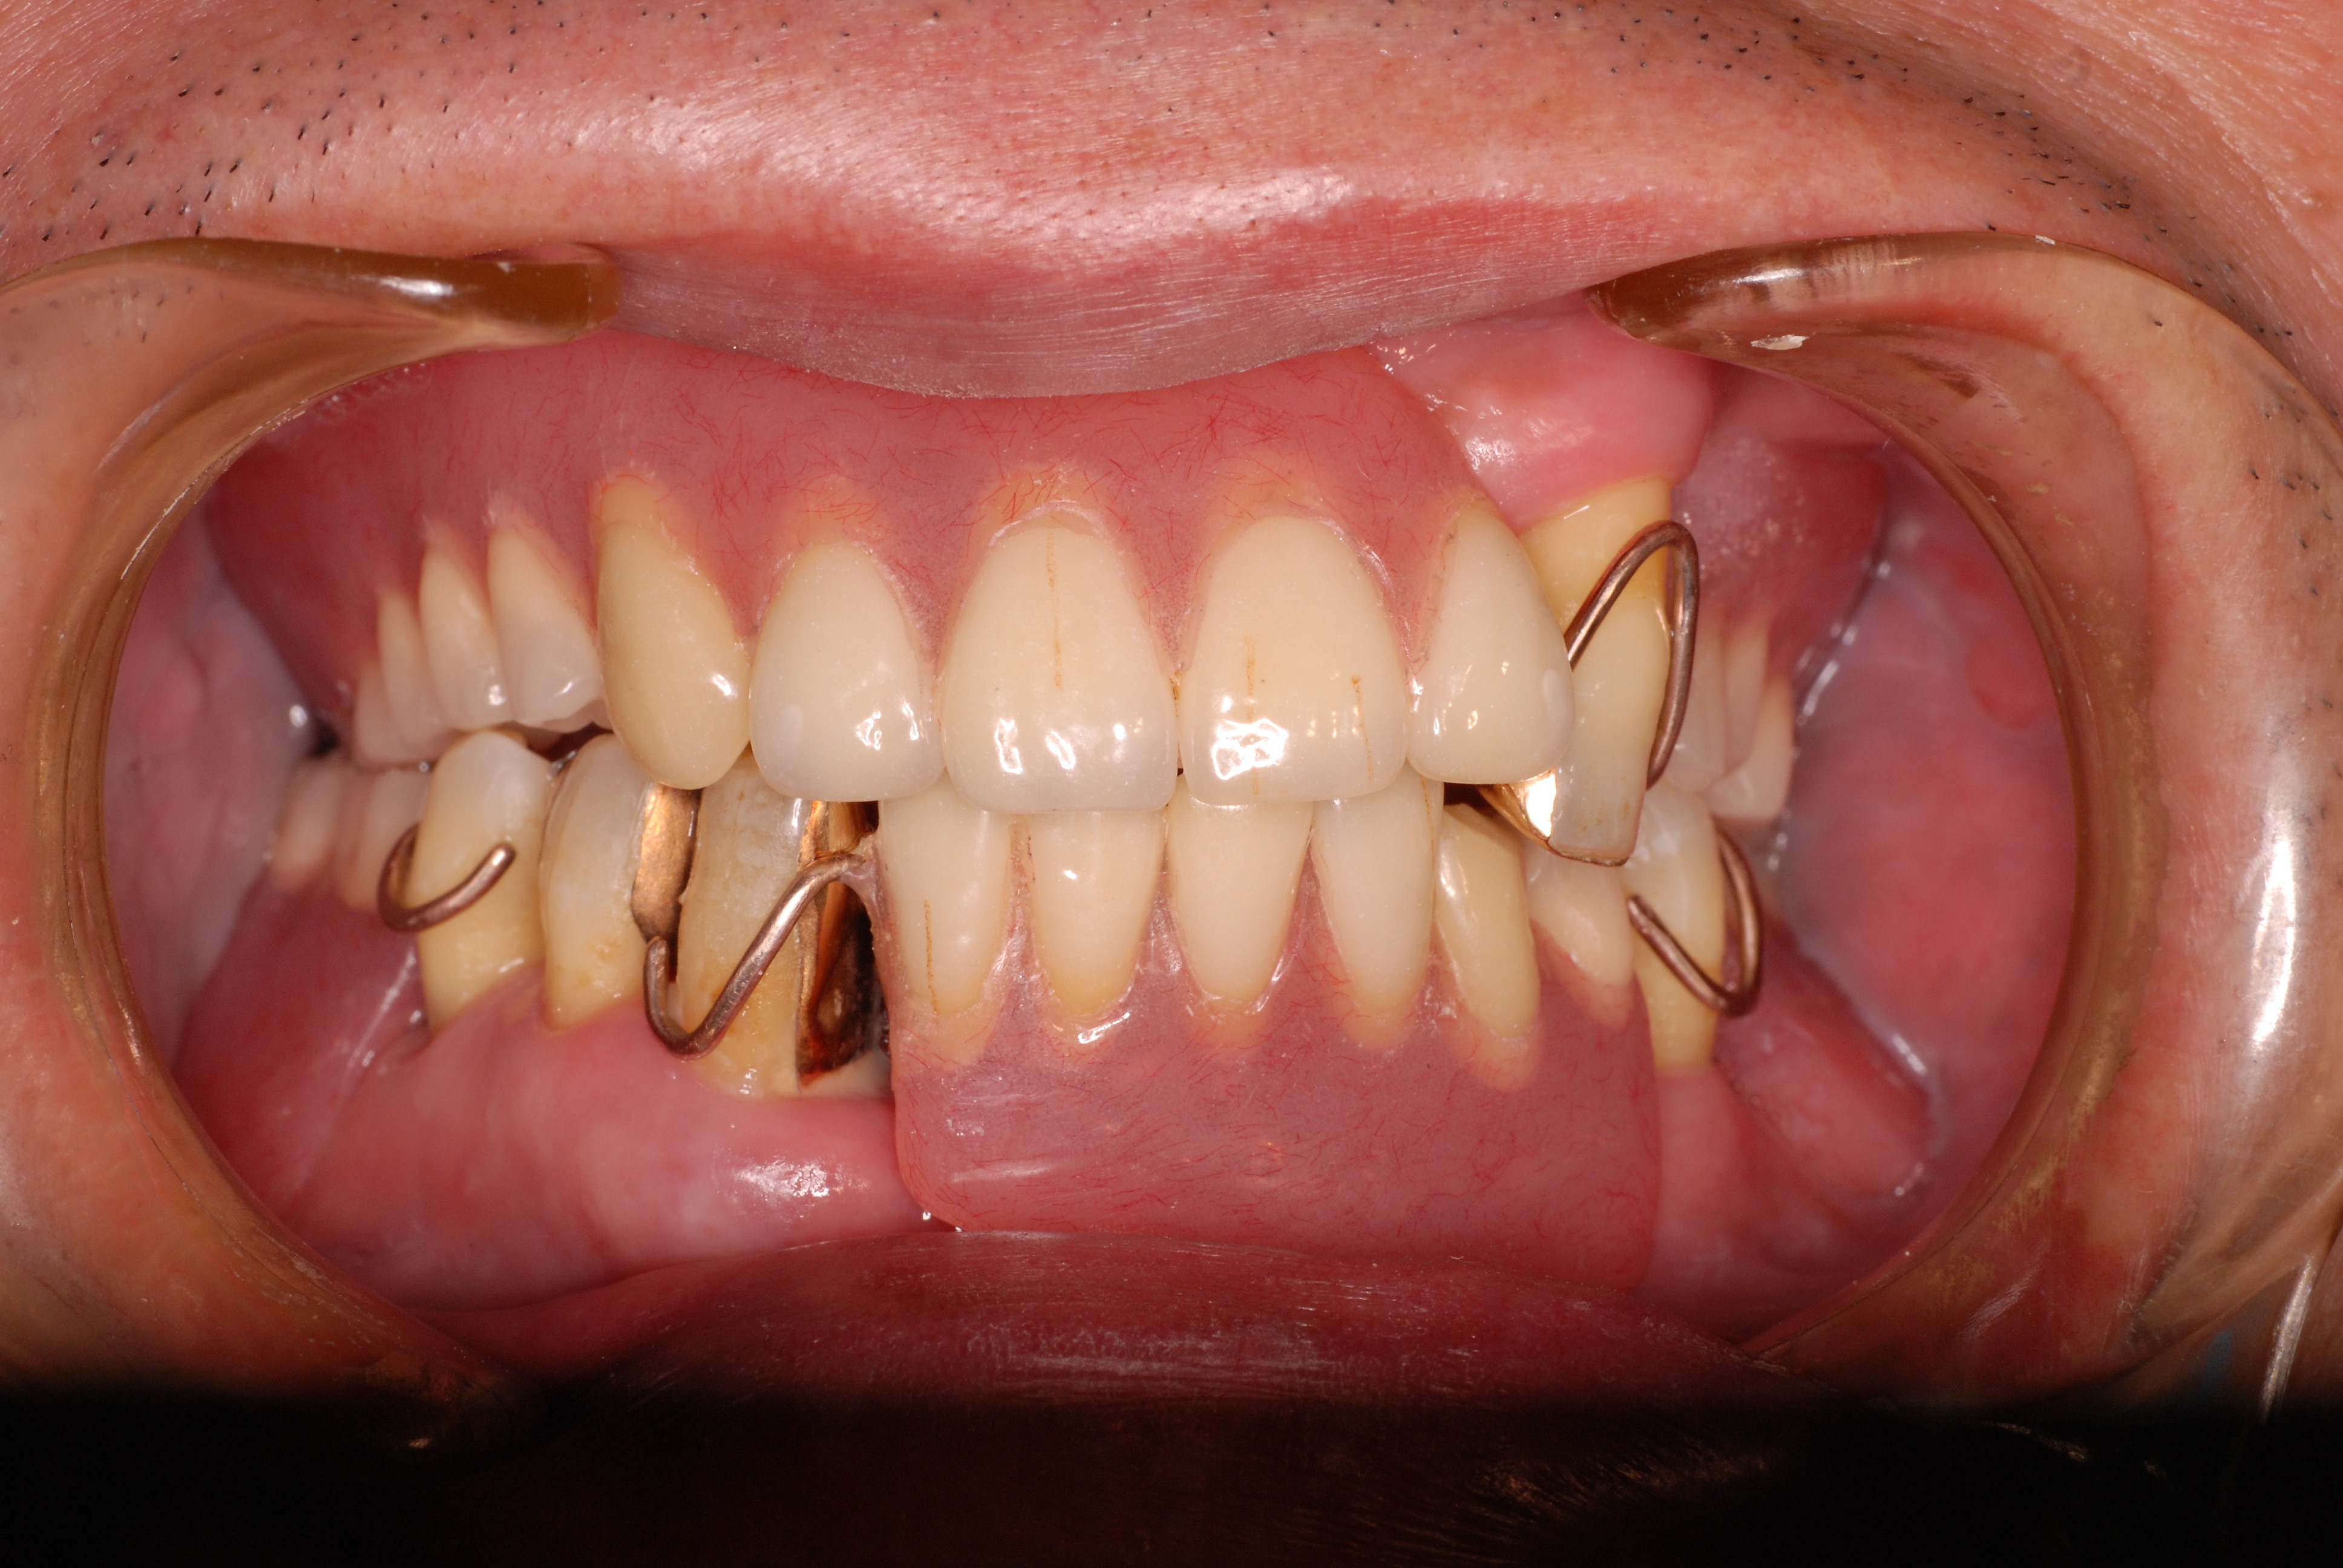

現実を見ればお口の中には“異物”である金歯、銀歯、セラミック、インプラントのオンパレードです。

これ等のものは、異物です。無い方が病気にならず健康でいられるのです。

その結果、歯科の潮流は保険にない、矯正や美容、インプラントぐらいしかやる気を出せなくなっているのです。

お口の中から差し歯、入れ歯、詰め物を追放しましょう!

必ずばい菌が侵入しないようにしてばい菌である虫歯を除去します。

銀歯の下はばい菌だらけです。こういうのはよくあります。取り残しですね。![treatment_05[1]](https://livedoor.blogimg.jp/netdental/imgs/3/a/3ad019d0-s.jpg)